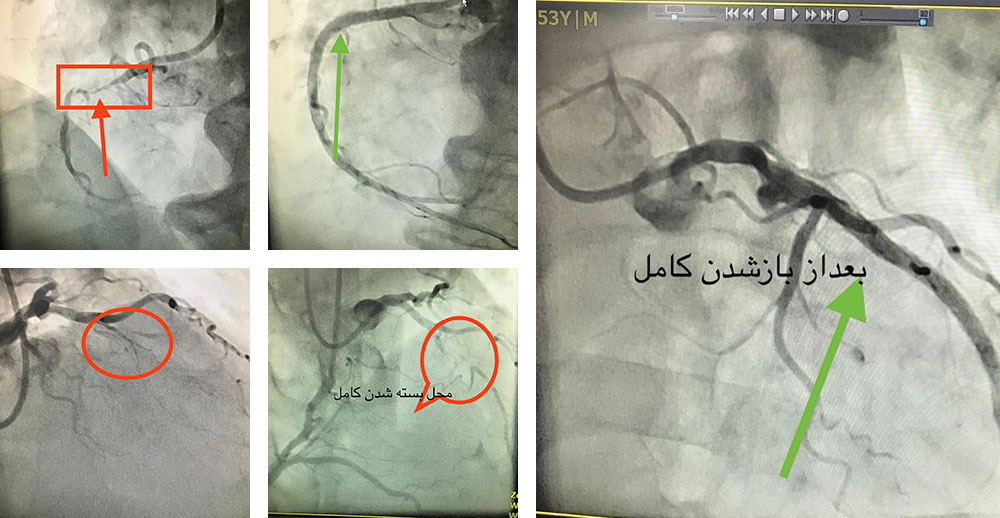

انسداد کامل رگ

انسداد کامل رگ آخرین سنگر ناگشوده ی آنژیوپلاستی بود که با تکنیک های جدید، تا ۹۰٪ امکان بازگشودگی بدون جراحی قلب باز را دارد. بیمار اول انسداد کامل رگ راست و دومی انسداد کامل رگ چپ داشتند. هر دو بیمار از طریق هر دو شریان دست راست وچپ درمان و روز بعد بی هیچ عارضه یی مرخص شدند. ایمان بیاوریم به اعجاز روش های نوین آنژیوپلاستی!